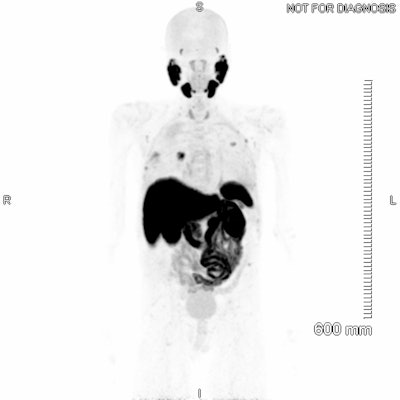

"Superscan" appearance for [F-18]-PSMA-1007.

The phenomenon of a “superscan” was first described in 1975 for bone scintigraphy and is considered to be widespread, intense, and largely symmetrical uptake of the osseous radiotracer, typically accompanied by minimal or absent tracer accumulation in the urinary system and soft tissues. This is generally a finding that occurs in technetium-99m hydroxymethylene diphosphonate (Tc-99m HMDP) bone scans, but there have been some reports of the “superscan” appearance with PET/CT, as well as some evidence of it occurring with Ga-68 PSMA PET.

The first F-18-PSMA-1007 PET study was performed at the Mater in April 2022. The patient had been diagnosed with prostate cancer more than a decade earlier, having multiple nodal, lung, and bone metastases. Despite ongoing treatment with gonadotrophin-releasing hormone agonists, his prostate-specific antigen (PSA) was continually rising.